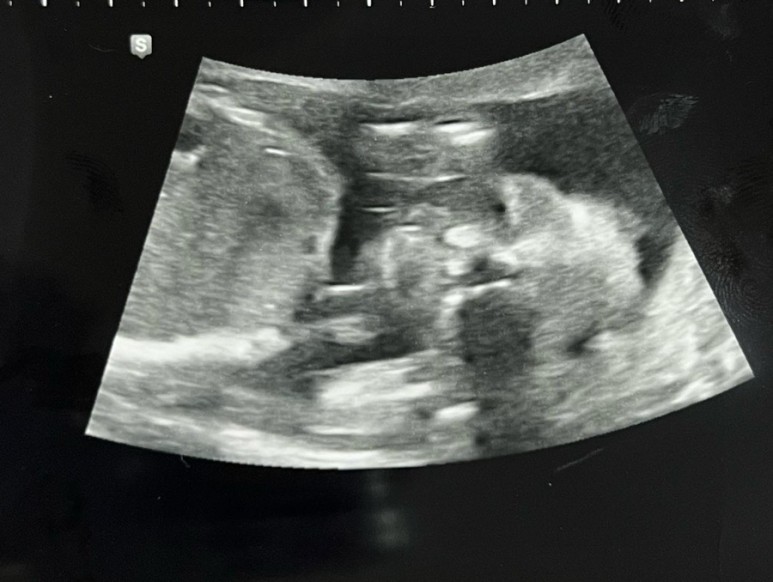

이젠 꽤 인간스러워져서 신기했어.15주 6일 병원에 가서 성별도 같이 보려고 했지만 호람이는 절대 보여주지 않았다.